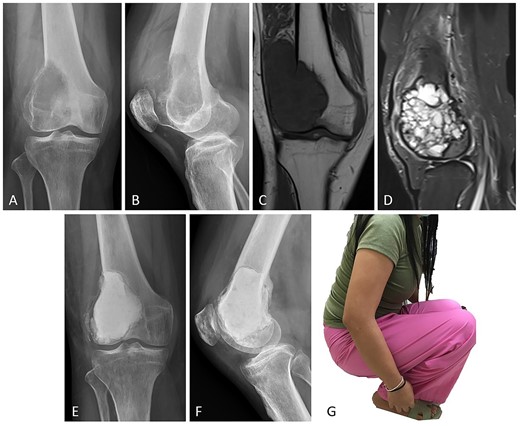

Case no. 13: (A–B) male, 32 years of age with GCTB at the distal femur with subchondral bone involvement, Campanacci grade III. (C–D) Preoperative T1-weighted coronal view MRI showing low-intensity with soft tissue extension and T2-weighted sagittal view MRI showing a heterogeneous high-intensity change with surrounding soft-tissue edema. (E–F) Radiograph at 26 months after extended curettage with hydrogen peroxide, argon beam coagulation, and cementation with hydroxyapatite bone substitution (packed above the subchondral bone). (G) MSTS score 86%.